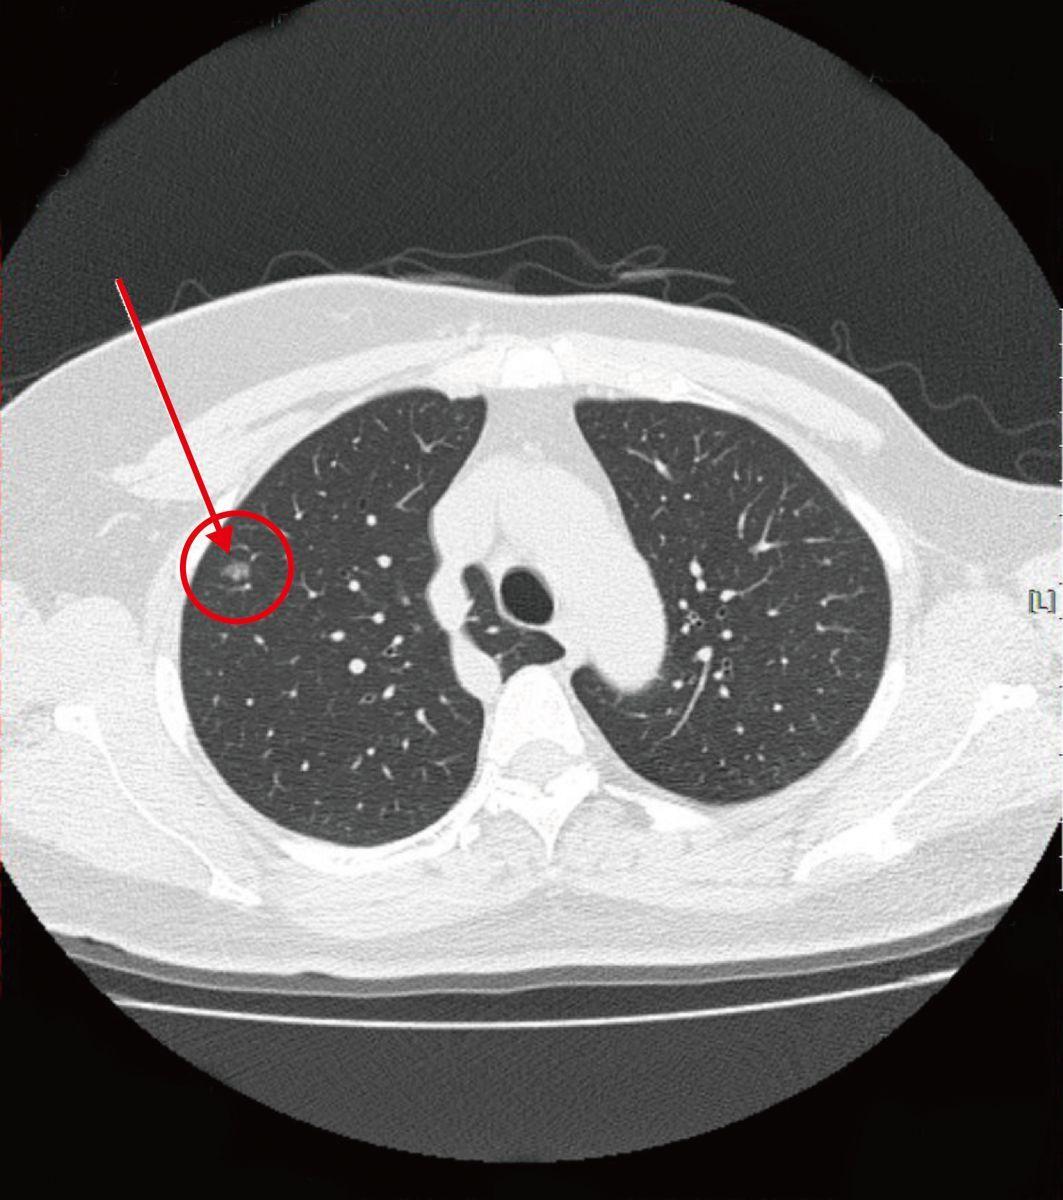

典型的右上肺腺癌的混合密度磨玻璃结节.